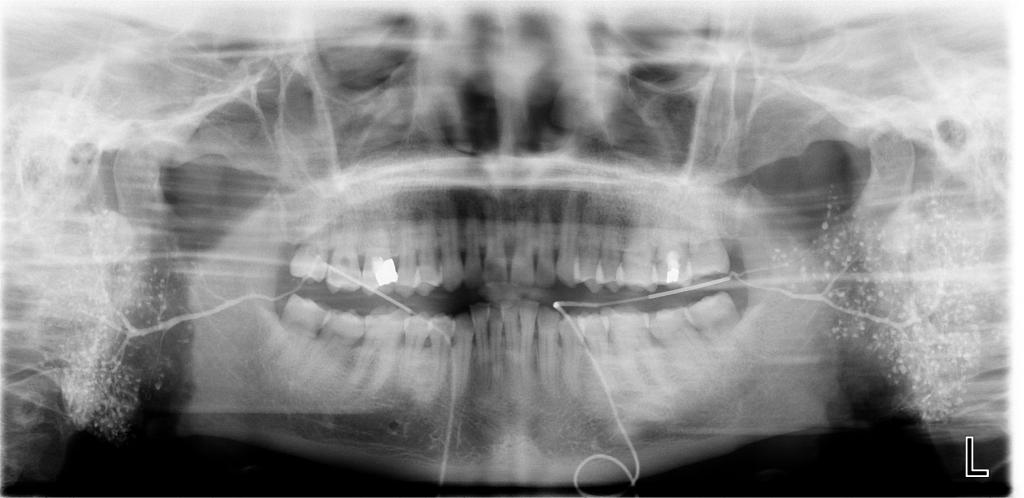

数字化口腔曲面体层片

常规开展:数字化根尖片/横断牙合片、数字化口腔曲面体层片、头影测量侧位/正位片、手腕骨片、颅颌面CBCT、牙齿CBCT的检查以及涎腺造影、窦道 瘘管造影。

诊断范围涉及牙体牙髓病、牙周病、阻生牙/多生牙定位、种植牙术前CT评估分析、颞下颌关节CT诊断分析、,颌骨及涎腺疾病、颌面发育畸形、正畸治疗辅助诊断等大部分颌面部疾病,为临床医疗提供强有力的支持。